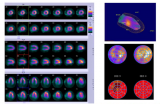

《心肌灌注显像质量控制和规范化报告书写》 - 张晓丽教授

中国核心脏病学的发展任重而道远,现状不容乐观,形势严峻。 2020-07-30 视频